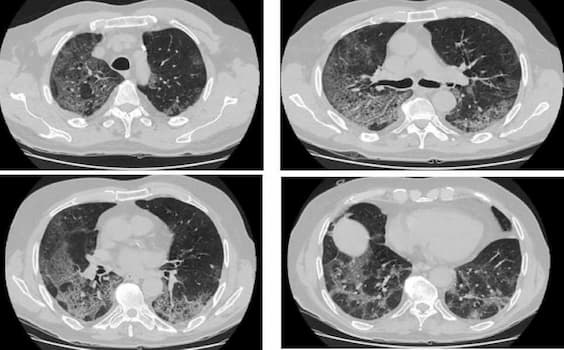

Hình ảnh xơ phổi ở bệnh nhân COVID-19.

Hình thành sẹo xơ vi thể ở nhu mô phổi

- Tình trạng xơ phổi

Khi xuất hiện tổn thương phổi do Sar-CoV-2, nhu mô phổi tổn thương sẽ là yếu tố thuận lợi cho viêm phổi bội nhiễm. Ở các bệnh nhân có viêm phổi lan tỏa trước đó, màng phế nang - mao mạch sau giai đoạn viêm sẽ lành dần, dịch viêm rút đi, các xác hồng cầu hay xác tế bào được dọn dẹp và các sẹo xơ li ti được hình thành.

Có thể hình dung quá trình này giống như một vết xước da nặng khi bị chà xát trên mặt đường, vết thương sẽ lành dần, lên da non và để lại một vết sẹo, khác biệt chỉ là các vết sẹo trong phổi thường rất nhỏ, chỉ nhìn thấy qua kính hiển vi, nên được gọi là tình trạng xơ hóa vi thể.

Các vết sẹo xơ li ti trong phổi nếu ít thì không ảnh hưởng, vùng phổi lành có thể bù được chức năng hô hấp, nhưng nếu sẹo xơ dày đặc hoặc các phế nang bị bít tắc nhiều, thì sẽ có thể làm phổi giảm co giãn khi hô hấp sau này.